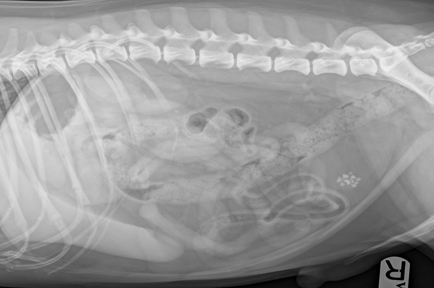

What is being shown on this radiograph?

Enlarged prostate (benign prostatic hyperplasia?)